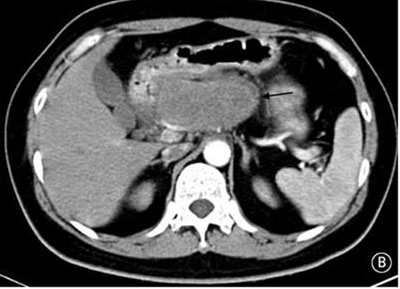

就诊时实验室检查结果显示严重高血糖(血糖水平为982mg/dL[55mmol/L])。腹部CT检查显示胰头部位出现一个9cm大小的肿块(如图B箭头所示)。空腹血清胰高血糖素水平为530pg/ml(正常值≤80pg/ml)。